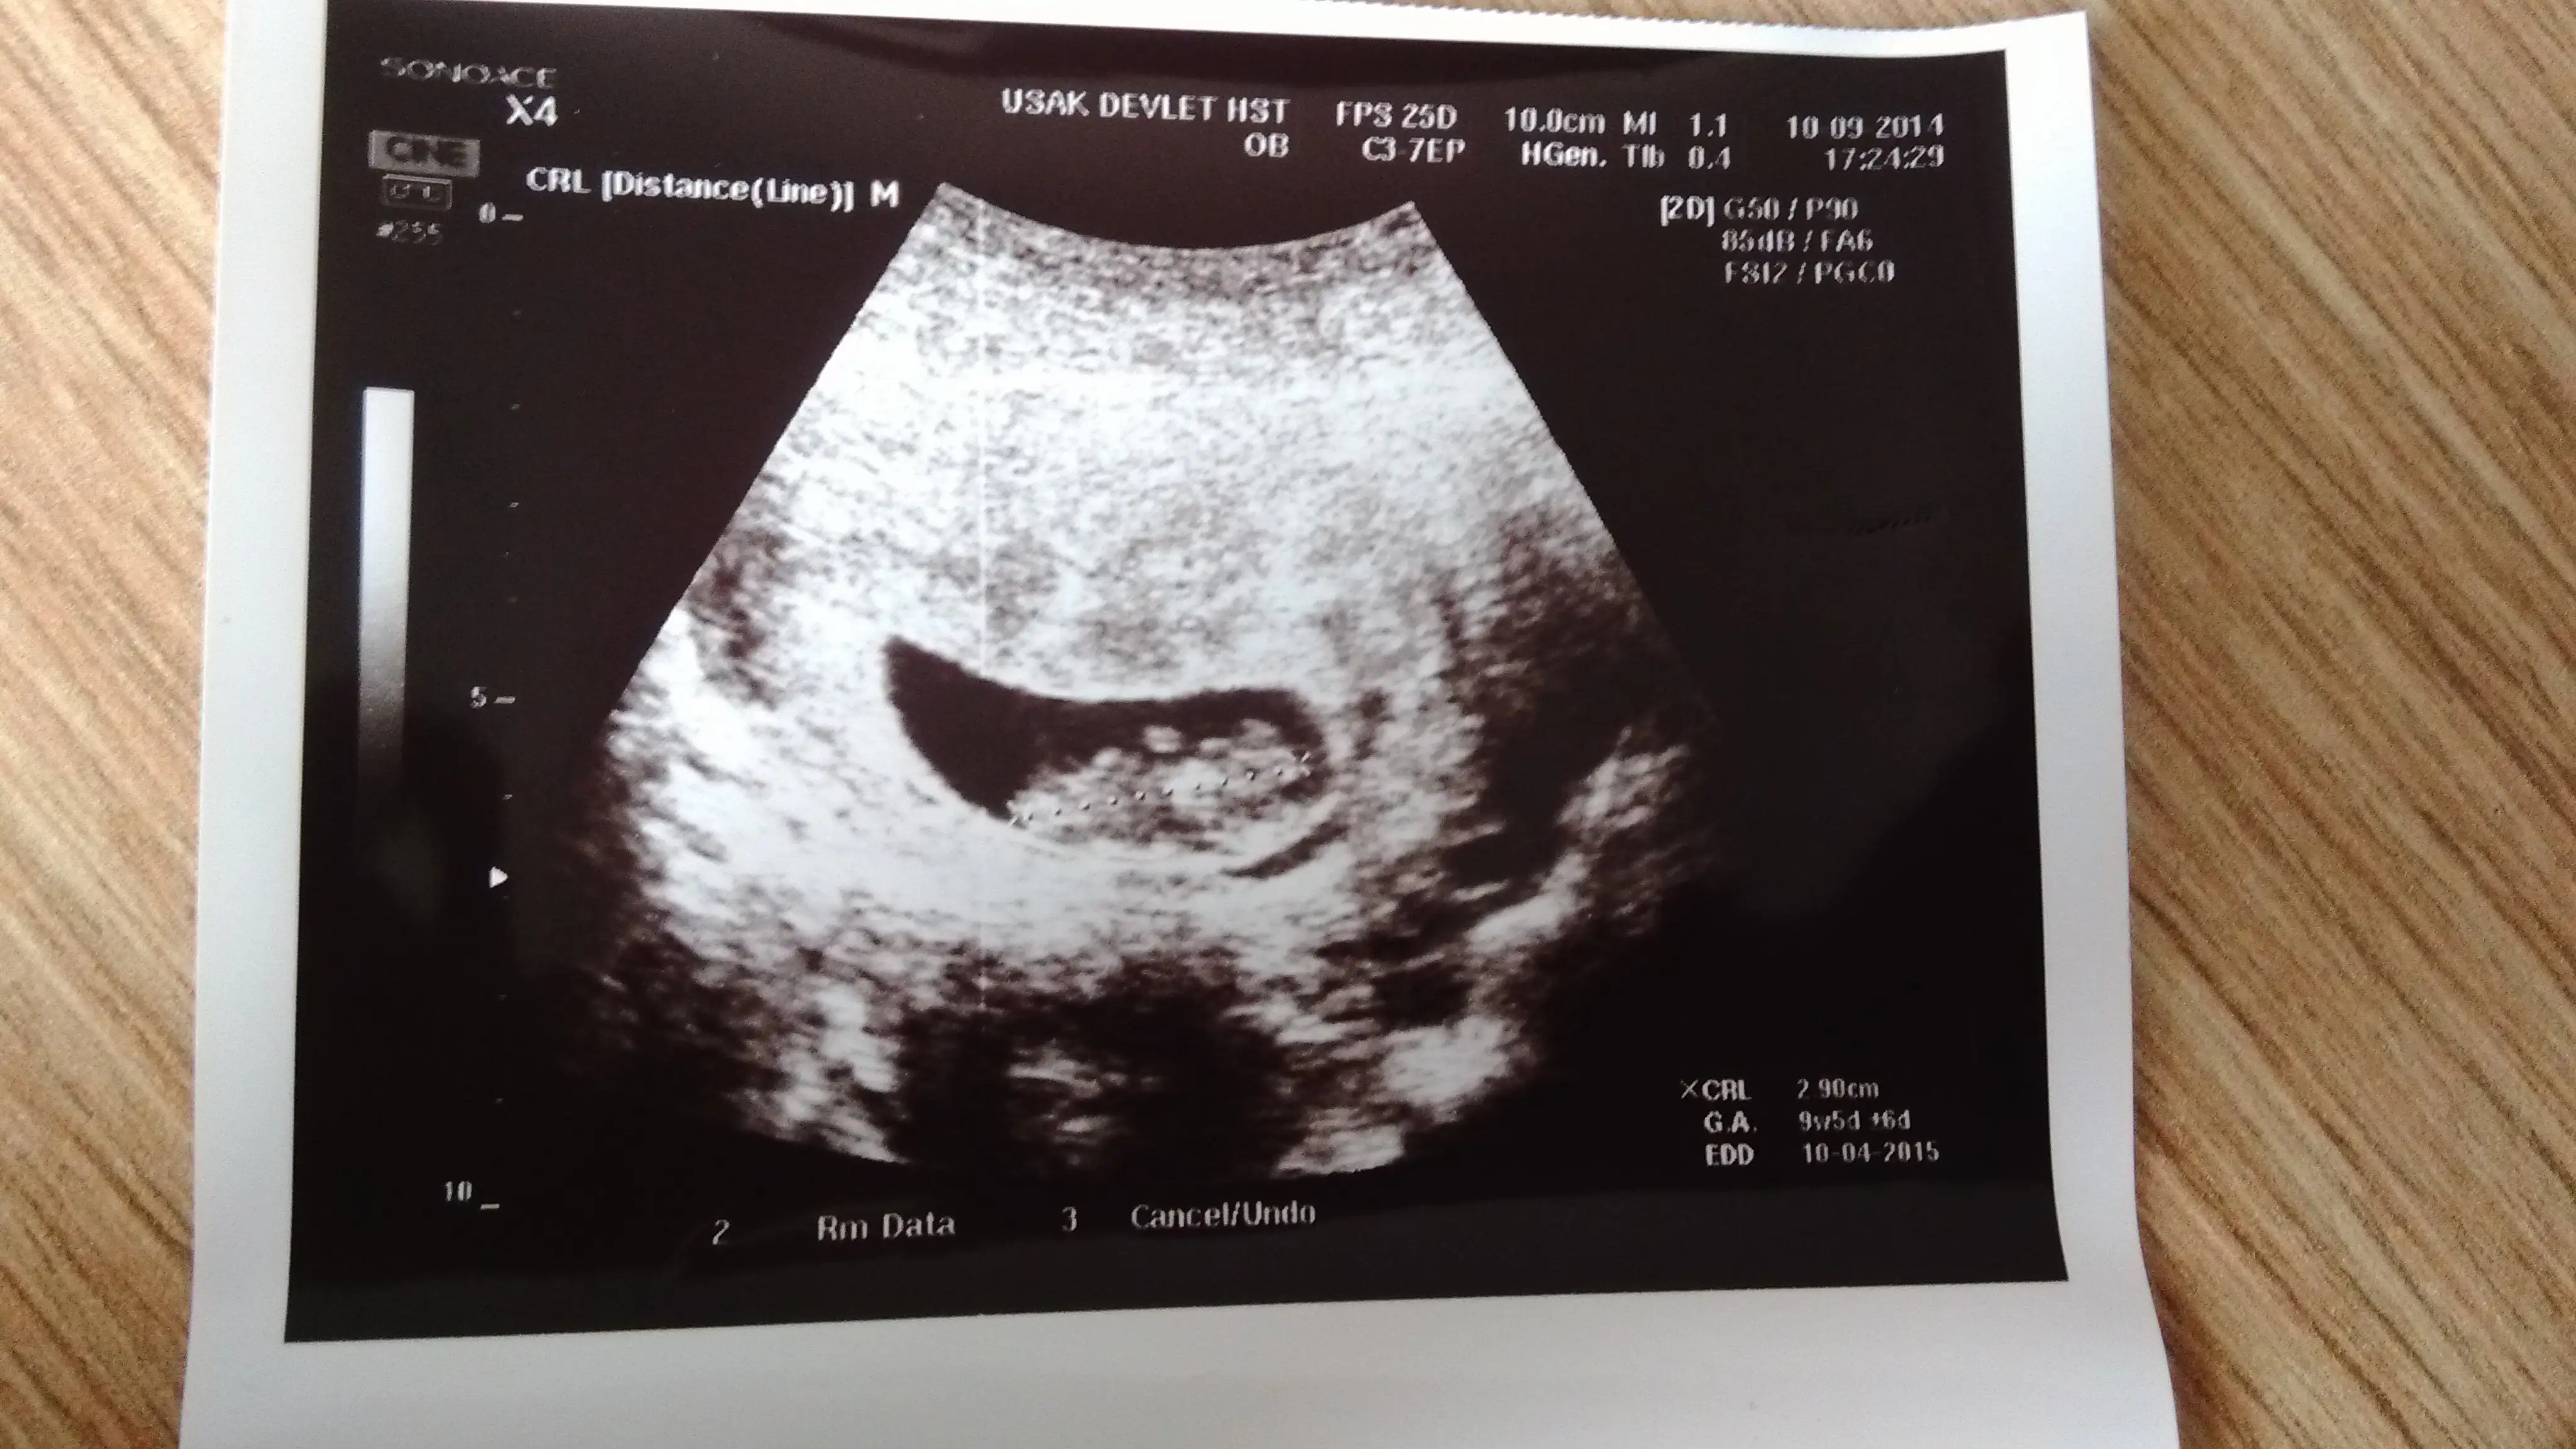

Bu da bizim 8+1 5 gün önden gidiyor. Oglumda fasulye gibi kesesi bunda yuvarlak...

benim bebişimi de tahmın eder misiniz hanımlar. bana göre mı yoksa karnıma tuttuğumdakı konumu mu önemli